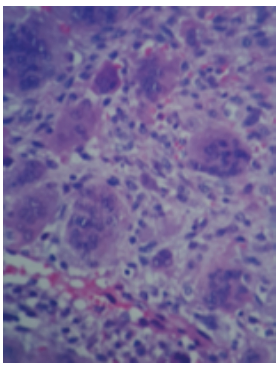

Paciente femenina de 8 años de edad, recibida en el mes de octubre de 2016, asintomática, sin antecedentes patológicos, alérgicos y quirúrgicos. Intraoralmente, presenta una masa tumoral de aproximadamente 6 x 6 cm a expensas de maxilar, que desplaza el primer molar y los molares temporales superiores izquierdos, no álgica a la manipulación (figura 1). En TAC contrastada se observa una lesión mixta de características osteolíticas, que involucra el seno maxilar, el reborde infraorbitario izquierdo y las celdillas etmoidales anteriores (figura 2, figura 3 y figura 4). Se realiza una biopsia incisional, obteniendo un diagnóstico de lesión central de células gigantes (figura 5). Se solicita estudio de niveles séricos de paratohormona y calcitonina, obteniéndose valores de laboratorios normales. Se inicia terapia esclerosante con triamcinolona, con aplicaciones semanales de 5ml de triamcinolona de 10mg con lidocaína 2% con epinefrina 1:100 000 UI (7). En enero de 2017, se presenta con dolor espontaneo e incremento exponencial de la lesión, causando deformidad hemifacial izquierda, obstruyendo en un 50 % la luz de la cavidad oral. Se interviene para escisión de lesión tumoral y curetaje, retirándose al 90% y se realiza además derivación de conducto parotídeo izquierdo. En marzo de 2017, acude a control con aumento de volumen intraoral nuevamente. Se informa a sus familiares sobre la existencia de otra terapéutica sustentada por diferentes publicaciones, para estas lesiones que no responden a los tratamientos con esteroides y a los quirúrgicos. Tras su aceptación se programa terapia antiangiogénica con interferón alfa 2ª vía subcutánea de 3 a 6 millones de UI semanales por 4 a 8 meses, iniciándolo a las 48h tras la cirugía (5). En abril, es reintervenida, sin complicaciones, para escisión quirúrgica de lesión central de células gigantes recidivante agresiva, y se inicia terapia con interferón alfa 2ª para reducción y esclerosis de tumor. Se solicita interconsulta a Servicio de Psicología a fin de mes, por datos de depresión. Se enfatiza esta relación con el medicamento, así como malestar general, astenia, somnolencia y afectación del estado general. El Servicio de Psicología diagnostica un estado depresivo leve, que no se considera indicativo para detener tratamiento con interferón alfa 2ª. En junio de 2017, se corrobora la esclerosis de la lesión a través de exploración con TAC de macizo facial, simple y contrastada. La paciente se encuentra sin datos de actividad tumoral, estado físico y psicológico en buenas condiciones, transcurridos 36 meses al día de hoy (figura 6 y figura 7).